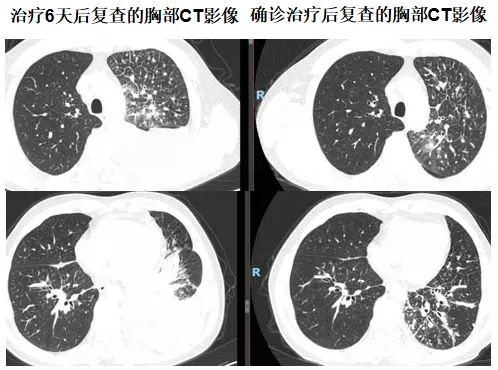

经过六天的规范治疗,患者胸闷、气短症状愈发明显。见此情形,延安市中医医院肺病科专家团队紧急为患者复查胸部CT。对比入院时的影像资料,发现左肺感染进展,胸腔积液增多,右肺下叶新发感染。肺病科的谢加利主任和艾克东副主任临危不乱,凭借多年积累的丰富临床经验和敏锐的专业洞察力,对患者的病情展开深入细致的分析。他们在仔细研读CT影像时,敏锐地捕捉到一系列异常细节:患者胸水单侧且发展迅速、左肺淋巴管增粗、胸水呈淡血性,结合胸水细菌培养+药敏结果(肺炎克雷伯菌感染)及结合药敏抗炎不佳的情况,考虑肺炎合并肿瘤可能性大。

时间紧迫,分秒必争。当务之急便是获取肺部病变组织的病理结果,才能为后续的治疗指明方向。与患者家属充分沟通后,为患者实施了CT引导下经皮左肺病变穿刺活检术,手术团队凭借精湛娴熟的技术,成功获取了病变组织样本。经过严谨细致的病理检测,最终确诊为左肺腺癌。在全体医护人员的悉心照料与专业治疗下,患者病情迅速得到控制并好转,患者的脸上重新绽放出久违的笑容。